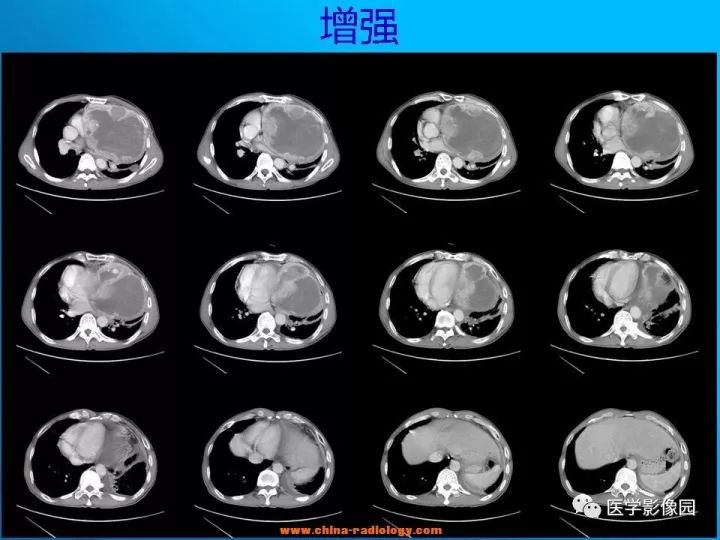

CT表现

1.肿瘤多为单发,平扫密度略低于肌肉,轮廓光整,呈类圆形或卵圆形,肿瘤较大时可为不规则形或呈分叶状,易囊变,常为囊实性,有包膜,可有钙化。

2.增强扫描多数病例肿瘤强化轻微,包膜可强化,少数病例可有较明显强化。

3.当肿块体积较大,并向周围侵犯,其内密度混杂,尤其是囊变、坏死明显;实性部分呈斑片状及网格状较明显强化;往往提示为恶性神经鞘瘤。